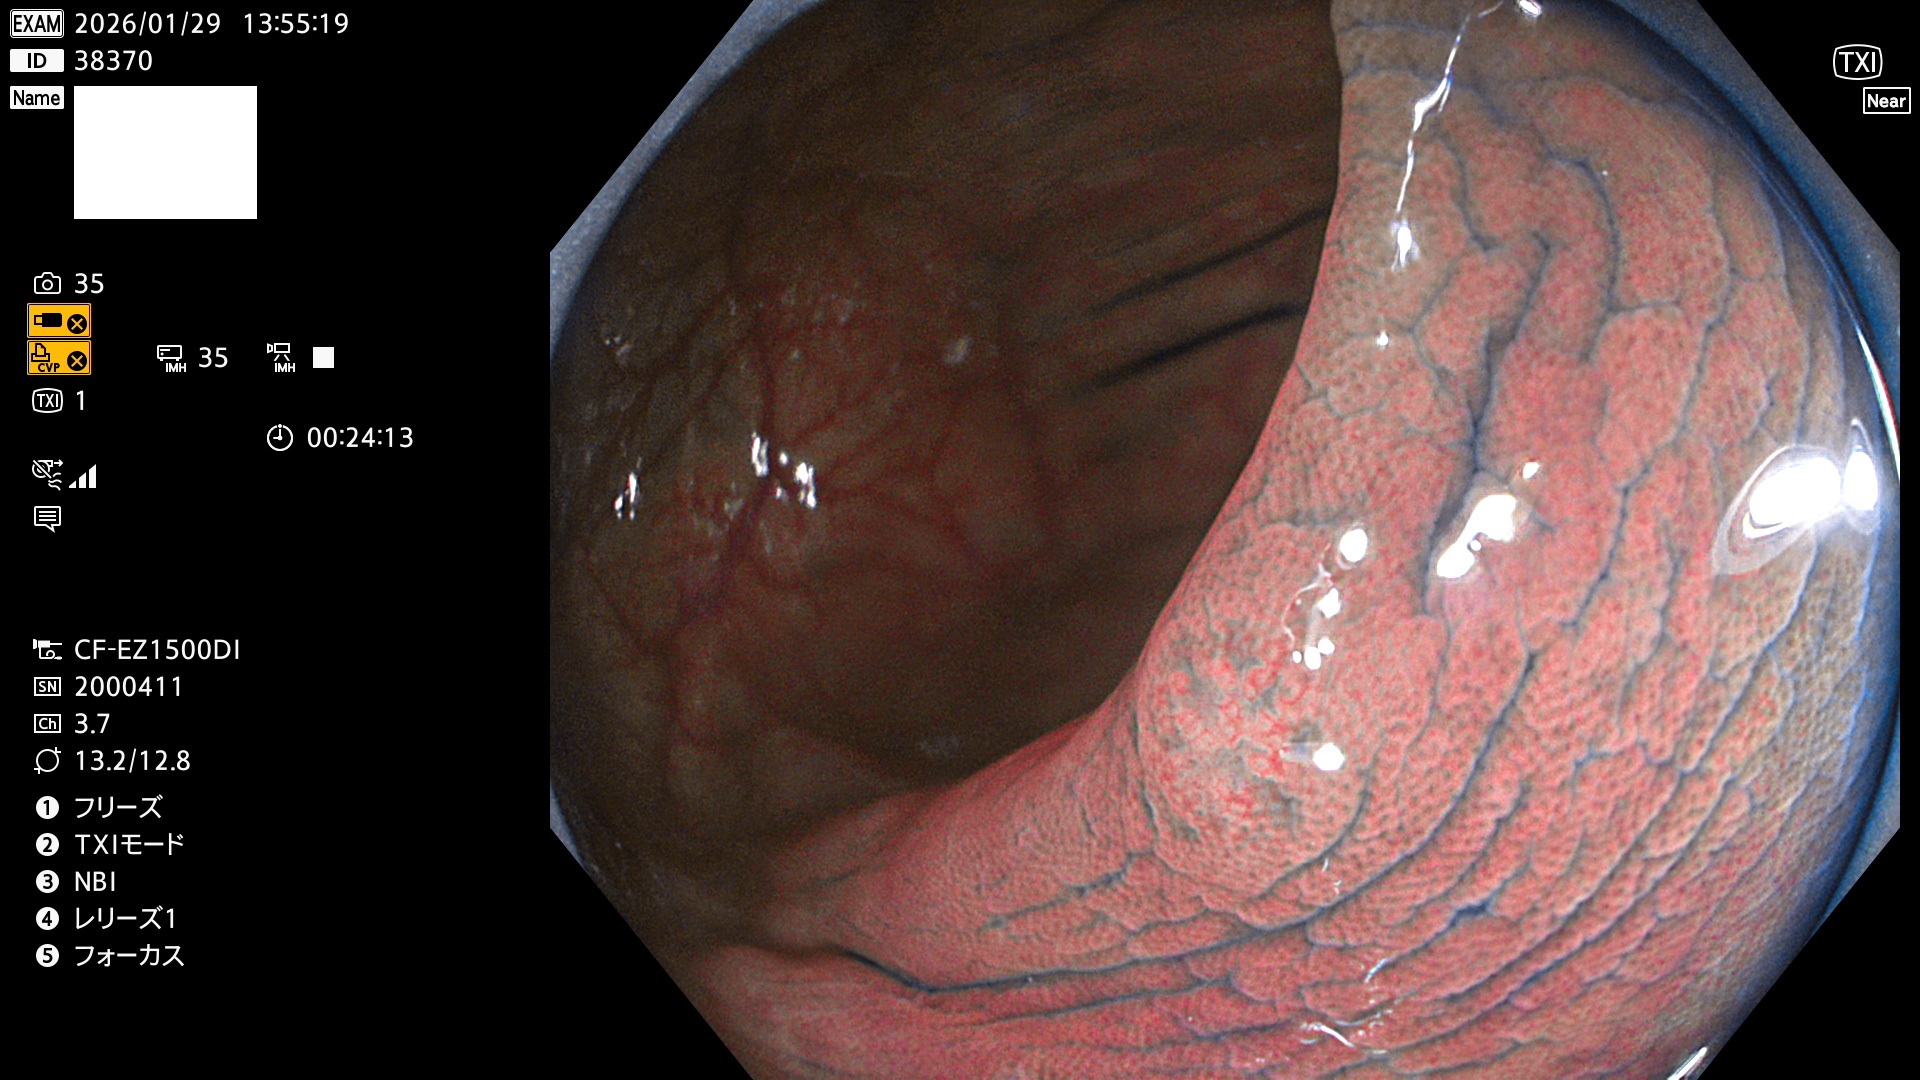

完全に平坦な物をUb、陥凹している物をUcと呼びます。Ubは認識が困難で、Ucはびらん(炎症)と紛らわしいために見落とされやすく、「内視鏡後・大腸癌」の原因になります。

専門的)Uc=De Novo癌? 内視鏡の解像度が低かった時代、このような説もありました。しかし今日の高精度内視鏡では良性の微小なUc型腺腫(APC遺伝子異常の腺腫)が日常的に見つかります。Ucこそが多段階発癌(Adenoma-Carcinoma Sequence)のMain Routeです。

毎週の検査(木・金・土・日)に発見されたUbとUc型・腺腫を、その週の日曜の夜にUPし1週間、提示します。

2026年1月29日〜2月1日の4日間(40件)10個 (Uc_ADR=10個/40人=25%)